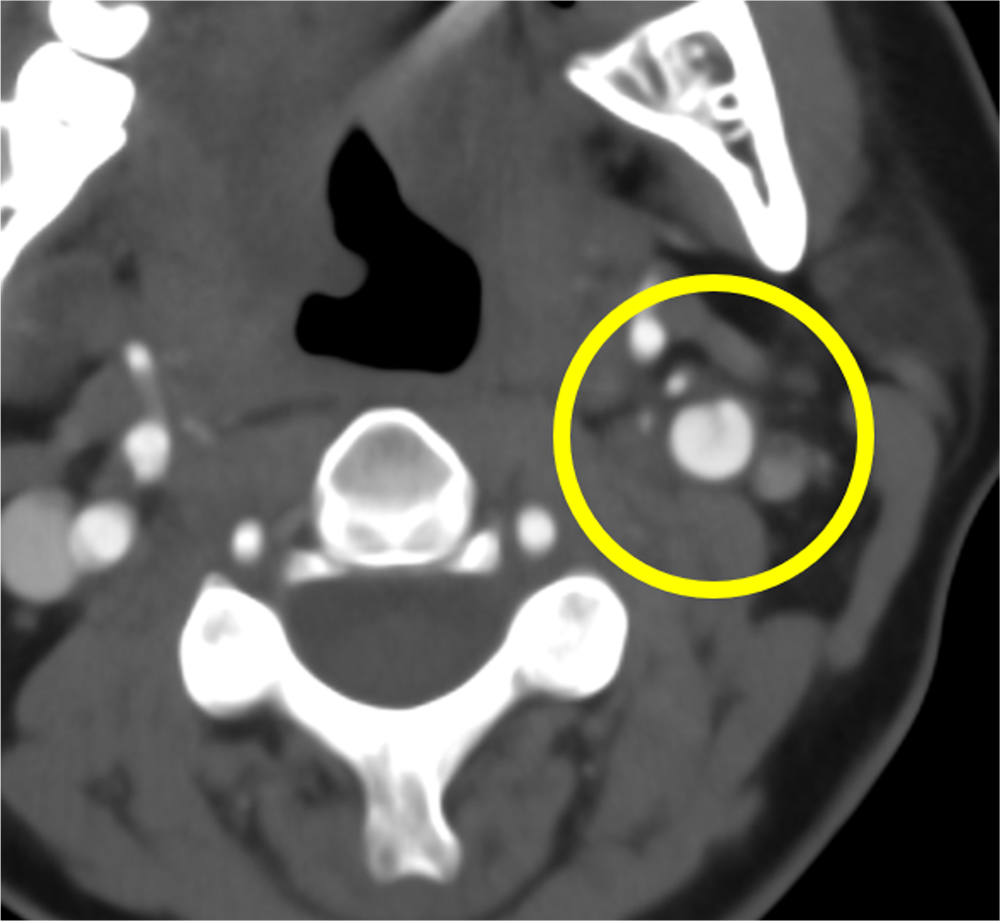

交通外傷後に構音障害が持続し、脳梗塞と診断された患者。内頸動脈解離による閉塞が疑われ、造影CTが施行された。造影CTで左内頸動脈の閉塞を指摘、原因として解離が疑われた。

また、茎状突起の過長はないが、解離部近傍に茎状突起先端が近接しており、茎状突起による内頸動脈解離が疑われたため、茎状突起切除術後に狭窄部ステント留置となった。

DSAでは周囲骨が subtractionされ、頸部エコーや MRA においては茎状突起が描出されないため、茎状突起の評価が十分に行うことができない。そのため、内頸動脈解離急性期での診断の際に、過長茎状突起の有無の評価や内頸動脈と茎状突起の位置を描出するのにCTA が有効であると考えられる。

茎状突起周囲は下顎骨や乳様突起に囲まれており、3D 画像のみでなくCTAの axial view の元画像などで茎状突起と頸動脈が近接していないか確認するのがよいと考えられる。

本症例では脳梗塞の原因として内頸動脈解離が疑われ、CTAが施行された。

CTAではターゲットとする血管を正確に描出することが必要であり、高容量のヨード造影剤を使用し、4.0ml/secの 速度で急速注入を行い、生理食塩水25mlで後押しした。また、撮影のタイミングが非常に重要であり、心機能など患者個々に応じた撮像のタイミングが必要となるため、当院ではボーラストラッキング法を用いた撮像を行っている。

今回は内頸動脈をターゲットとしたため、大動脈弓部にROIを設定した。画像再構成では血管走行や解離部位を詳細に評価するため、0.5mmにスライス厚を設定する。